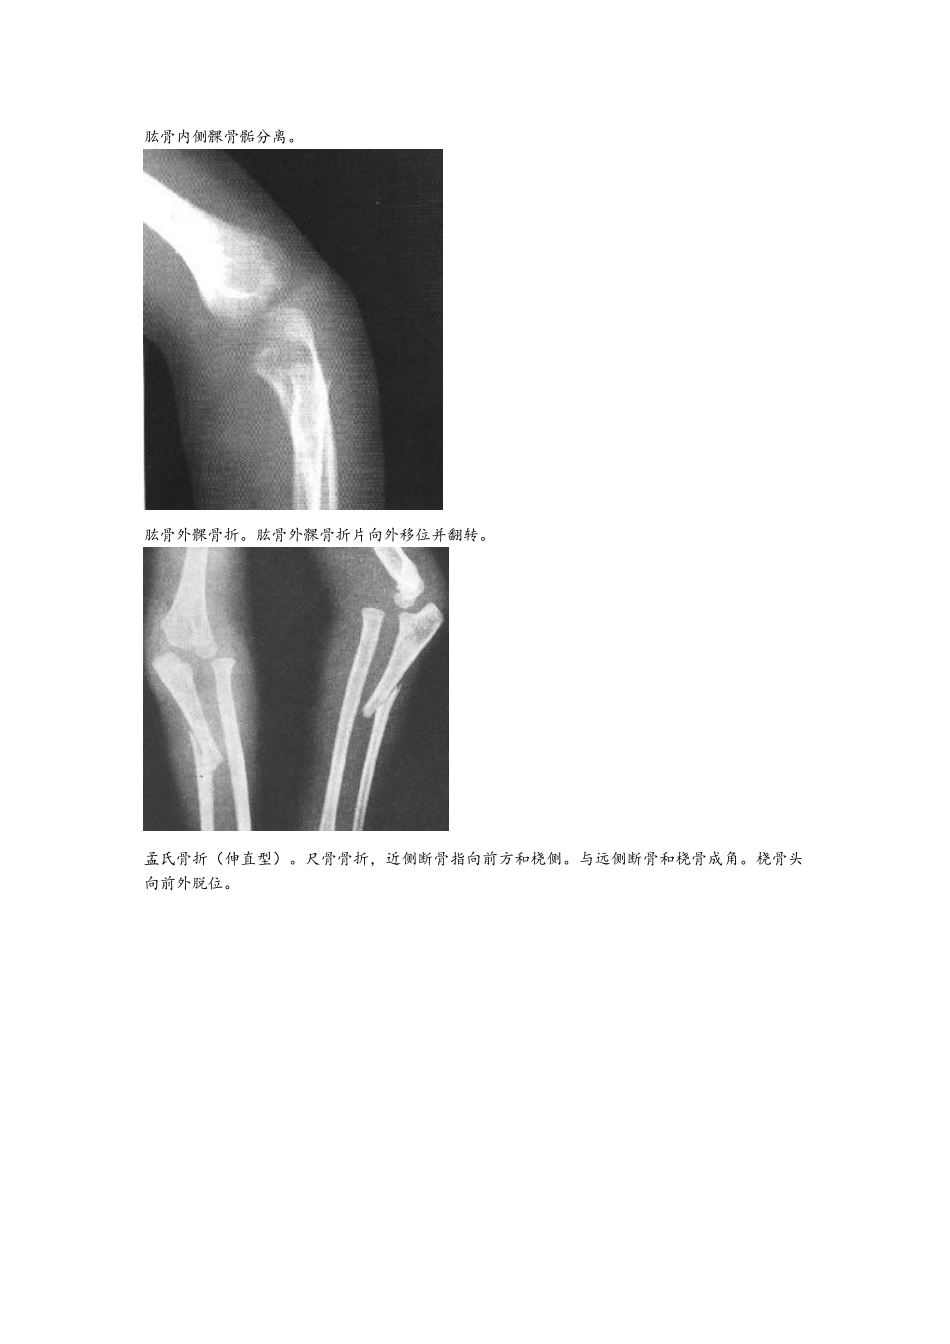

骨折图片大全!请进------锁骨骨折。锁骨骨干中段横断骨折。断端向上移位,形成凸向上之成角畸形。肩胛骨粉碎性骨折。肩胛骨外缘见一垂直形骨折线,上缘尚见星芒状骨折线。肱骨外科颈骨折(外展型)。肱骨骨干骨折。远侧断骨向上外方移位,附近有小碎骨片。肱骨髁上骨折。骨折线呈不规则横形,远端骨片稍向掌侧移位。肱骨内侧髁骨骺分离。肱骨外髁骨折。肱骨外髁骨折片向外移位并翻转。孟氏骨折(伸直型)。尺骨骨折,近侧断骨指向前方和桡侧。与远侧断骨和桡骨成角。桡骨头向前外脱位。盖氏骨折。桡骨中下 1/3 骨折,伴远端尺桡关节脱位和尺骨茎突骨折。柯雷氏骨折。桡骨下端横形骨折,远端断骨向背侧倾斜移位,侧位片呈“匙”样畸形,伴尺骨茎突骨折。史密斯骨折。腕舟骨骨折。腕舟骨中部可见透亮线。第一掌骨基底部骨折。下肢骨折图片 股骨颈骨折腓骨下段螺旋形骨折并踝关节半脱位胫骨下段斜形骨折尾指近-中节骨粉碎性骨折并完全性脱位跟骨骨折图片